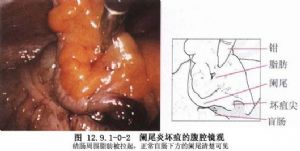

急性闌尾炎是外科很常見的一種疾病。闌尾切除術是最爲普通、常行的手術之一,但有時很困難,因此,對每一例手術均須認真對待。急性闌尾炎是小兒最常見的急腹症。由於小兒闌尾壁薄,穿孔率高;腹腔對感染的侷限能力差,一旦穿孔常造成瀰漫性腹膜炎;同時小兒又多因診斷延誤而未能早期治療,所以臨牀所見小兒闌尾炎病情較重。因此,小兒闌尾炎一旦確診,應立即手術治療(圖12.9.1-0-1,12.9.1-0

-2)。